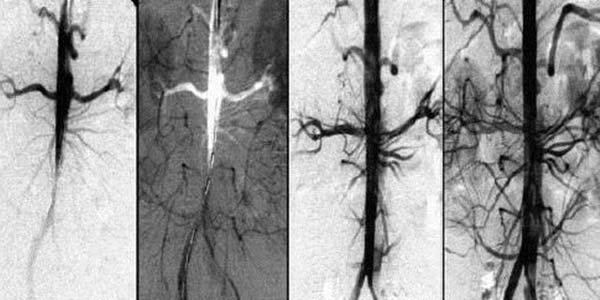

Przez 1,5 miesiąca przyjmowania Cardiotonus przywracane jest krążenie krwi o 99,71%.

Krążenie krwi zostaje przywrócone systemowo – we wszystkich naczyniach, tętnicach i naczyniach włosowatych.

Cardiotonus to know-how, duma naszych naukowców. Zapewnia prawie 100% oczyszczenie naczyń krwionośnych dzięki aktywnym frakcjom CO2 ekstraktów, które wnikają w blaszki cholesterolowe i rozpuszczają je od wewnątrz.

Rozpuszcza blaszki miażdżycowe, skrzepy krwi i wapń. Zwiększa światło naczyń krwionośnych do 99,71% normy i przywraca krążenie krwi.